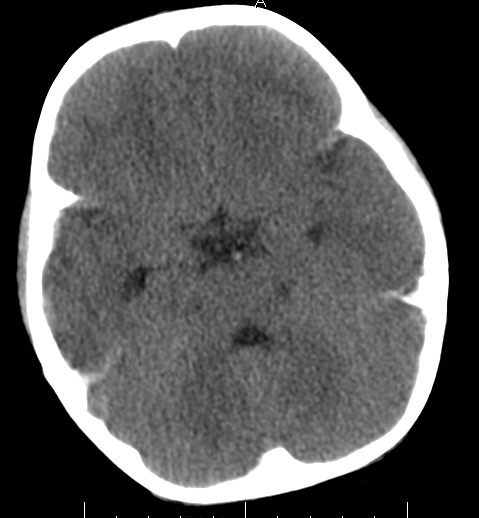

女,3岁,头部外伤一小时。半卵圆中心低密度是什么意思,病灶?侧脑室?请指教。

正常表现

幼儿正常脑白质表现,长期观察,必要时mr

从层面看不是侧脑室,考虑低密度变,建议mri。

不是侧脑室,考虑正常脑白质。为慎重,建议mr!